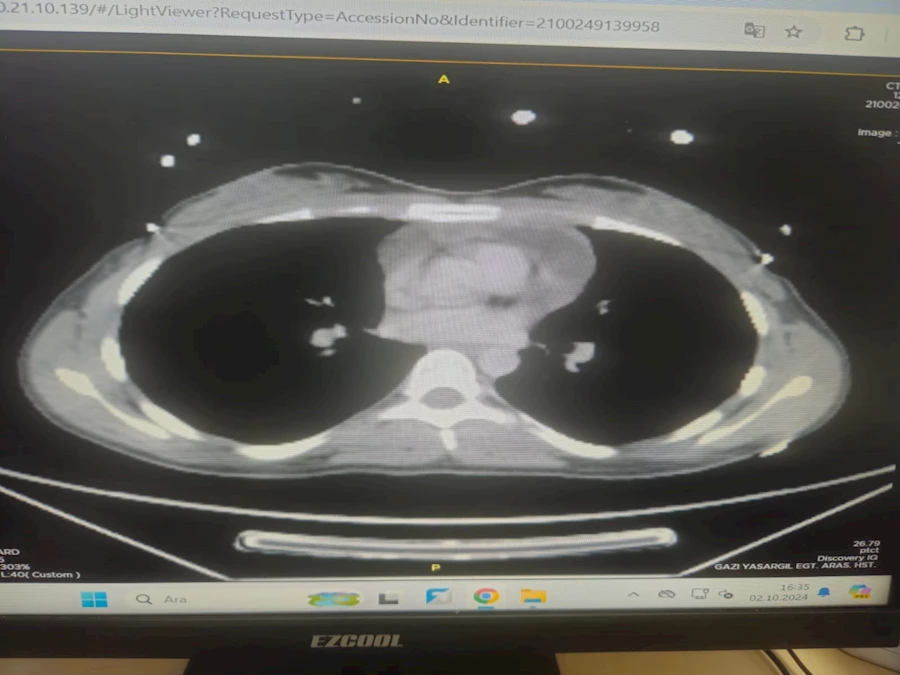

EMEK HABER- Diyarbakır Gazi Yaşargil Eğitim ve Araştırma Hastanesi’nde, 21 yaşındaki bir kadın hastaya, göğüs kafesinin ön duvarında bulunan yaklaşık 4 cm’lik kitlenin başarılı bir şekilde çıkarılması için kapalı akciğer ameliyatı (VATS) yapıldı.

Hastane yetkililerinden alınan bilgiye göre, hasta göğüs kafesindeki kitle şikayetiyle polikliniğe başvurdu. Yapılan tetkiklerin ardından ameliyat kararı alındı ve kapalı yöntemle gerçekleştirilen akciğer ameliyatı başarıyla sonuçlandı. Ameliyat ekibi; Video Yardımlı Torakoskopik Cerrahi (VATS) adı verilen bu modern yöntemi kullanarak, göğüs kafesine küçük bir kamera yardımıyla girerek operasyonu tamamladı. Bu teknik, eskiden kullanılan ve göğüs kemiğinin (sternum) açılmasını gerektiren klasik yönteme kıyasla minimal invaziv bir yöntem olmasıyla dikkat çekiyor.